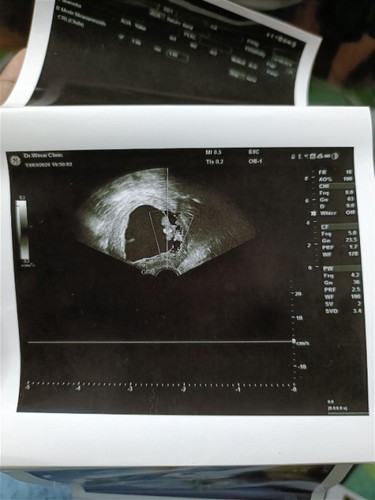

สอบถามหน่อยค่ะ มีเลือดออก และไปหาหมอ หมอซาวด์ดูบอกว่าไม่เห็นหัวใจน้องเต้น หมอบอกว่าเด็กหยุดการเติบโตตั้งแต่8วีค ตอนนี้12วีคแล้ว ก่อนหน้านี้ไม่มีอาการไรเลย เพราะไปฝากท้องตอน8วีค 3วัน แม่ๆๆบ้านไหนเป็นแบบนี้บ้าง ยังพอมีปาฏิหาริย์มั้ยค่ะ เพราะท้องแรกก็เด็กหยุดการเติบโต คนนี้ท้อง2ก็เป็นอีก กังวนมากๆๆ อยากมีลูกสักคน